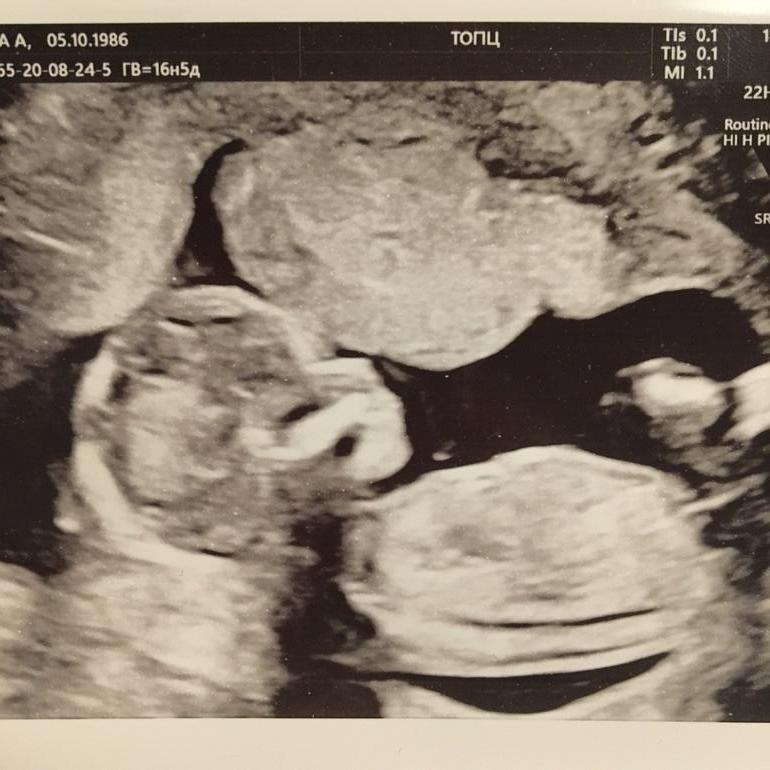

А вот и фотография нашей кнопочки 💘

Сначала она так сладко причмокивала во сне, а потом как начала брыкаться, видимо реагируя на датчик УЗИ 🙈🐒

Я смотрела на ее кульбиты и удивлялась, что живот продолжает молчать 🤗 Жду шевелюшек со страшным нетерпением!